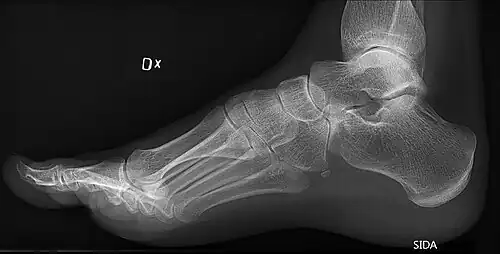

On weightbearing projectional radiography, pes cavus can be diagnosed and graded by several features, the most important being medial peritalar subluxation, increased calcaneal pitch (variable) and abnormal talar-1st metatarsal angle (Meary's angle).[17] Medial peritalar subluxation can be demonstrated by a medially rotated talonavicular coverage angle.[17]

![Weight-bearing lateral X-ray showing the measurement of calcaneal pitch, which is an angle of the calcaneus and the inferior aspect of the foot, with different sources giving different reference points.[18] Calcaneal pitch is increased in pes cavus, with cutoffs ranging from 20° to 32°.[17]](./_assets_/Calcaneal_pitch.jpg)

Same lateral X-ray showing the measurement of Meary's angle, which is the angle between the long axis of the talus and first metatarsal bone.[17] This example is slightly convex downward. An angle greater than 4° convex upward is considered pes cavus.[17] -

Foot with pes cavus (and os peroneum).